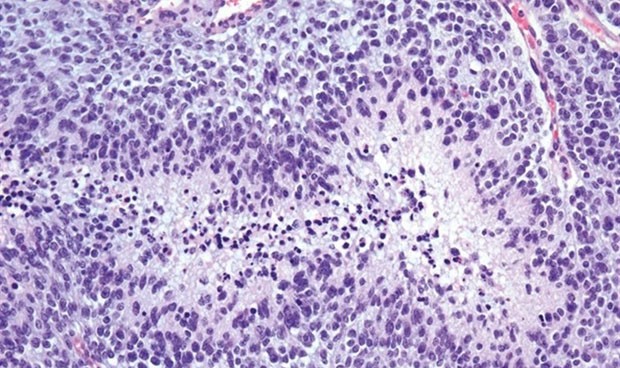

El cuerpo tiene ejércitos de glóbulos blancos que ayudan a combatir las bacterias, los virus y las células cancerosas. Esta constelación de células constituye el sistema inmunológico. "Una de las razones principales por las que el glioblastoma es tan agresivo es que apaga el sistema inmune", explica Clark C. Chen, el autor principal de este estudio, que se ha publicado en la revista Advanced Therapeutics.

La inmunoterapia funciona activando los glóbulos blancos que están presentes en muchos tipos de cáncer. Por razones que no están claras, los glioblastomas contienen pocos glóbulos blancos. Por lo tanto, no hay nada que activar en la inmunoterapia.

Para solucionar esta situación, el equipo de investigación inyectó partículas de sílice hueca (una forma de vidrio) en los glioblastomas para facilitar el reclutamiento de glóbulos blancos. Los tumores inyectados fueron tratados con ultrasonido focalizado de alta intensidad (HIFU). Este ultrasonido 'infló' las partículas de vidrio para romper las células cancerosas, liberando proteínas que atraen a los glóbulos blancos.

Al modular el ultrasonido de alta frecuencia, los investigadores pudieron crear diferentes temperaturas bajo las cuales se rompieron las células cancerosas. "Impresionantemente, la inmunoterapia solo funciona cuando el ultrasonido se ajusta para mantener una temperatura corporal estable a medida que se rompen las células cancerosas. Las temperaturas que se desvían demasiado de la temperatura corporal parecen comprometer la eficacia de los glóbulos blancos", detalla Clark C. Chen.